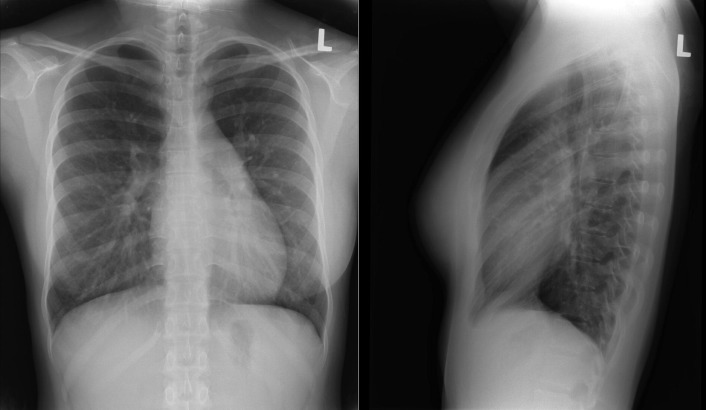

See Figures 18-5 to 18-31 . Possible findings are discussed in the following sections.

Left-to-right shunts initially result in volume overload of the chambers carrying the shunt volume, causing enlargement of the volume-overloaded chambers and an increase in pulmonary blood flow. If the amount of pulmonary blood flow is sufficiently high, obliterative disease of the pulmonary arterioles develops (“pulmonary vascular disease”), resulting in pulmonary hypertension. The chest radiographic appearance of pulmonary hypertension is one of centralization of pulmonary flow and accelerating enlargement of the right-sided chambers.